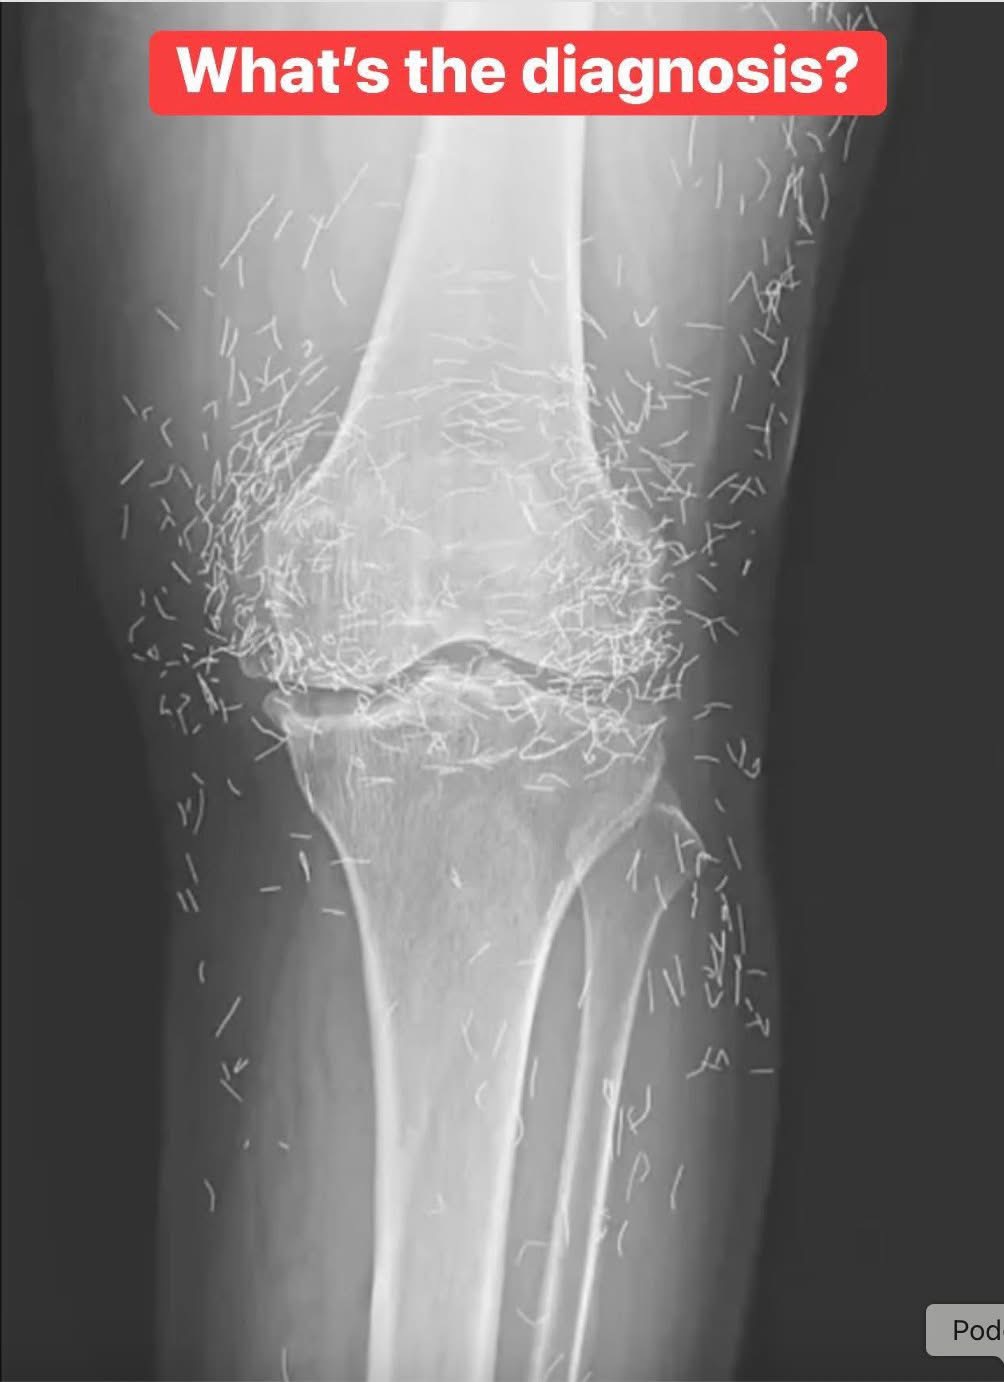

Doctors find โgold mineโ in womanโs knees

When a 65-year-old South Korean woman went in for knee pain, doctors werenโt expecting to strike gold. But thatโs exactly what they found. Unwanted stomach issues Living with osteoarthritis can be incredibly challenging. The condition gradually wears down the cartilage in your joints, leading to stiffness, swelling, and persistent pain that can make even simple…